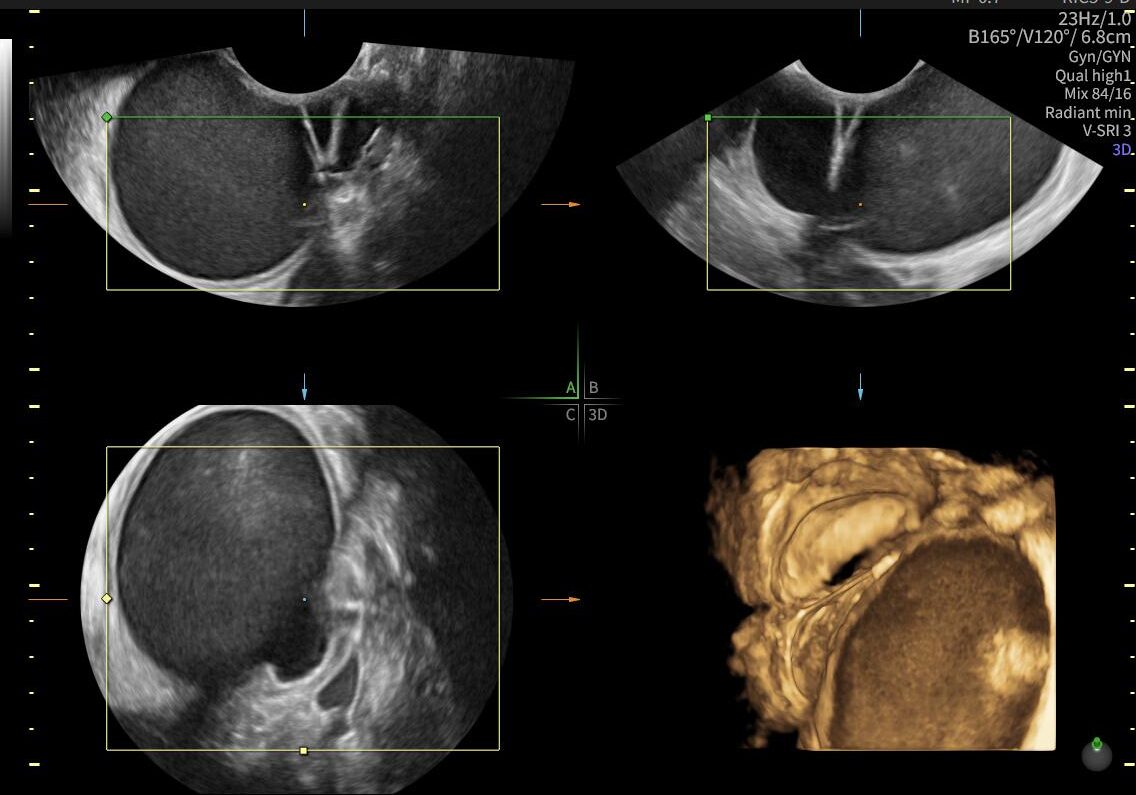

La ecografía ginecológica es un estudio por imágenes no invasivo que permite evaluar de forma precisa el útero, los ovarios y el sistema reproductor femenino. Es una herramienta fundamental para la detección temprana de alteraciones ginecológicas, el seguimiento de tratamientos y los controles preventivos.

En OBGYN Perú, realizamos ecografías ginecológicas con equipos de alta resolución, garantizando resultados confiables y una atención médica especializada.